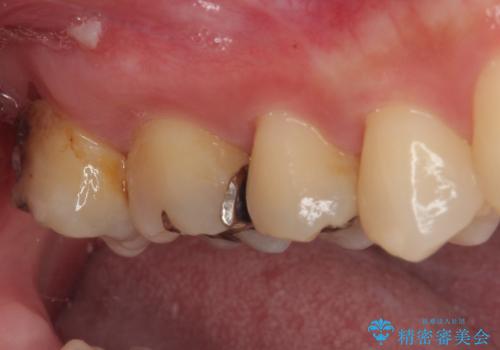

- 元々むし歯があったものの、処置が困難とのことでしたが、矯正治療を終えたので処置をしたいとのことで来院された患者様です。

左右ともに最後臼歯が頬側に顕著に突出しており、むし歯になってしまったことが想像されました。

矯正治療により処置が可能な位置に歯が移動したため、オールセラミッククラウンにて補綴治療を行うこととしました。

歯列が移動したとはいえ、左右ともに後方傾斜しており、むし歯の除去、形成(形を整える)、型取りの全てが非常に困難な処置となりました。